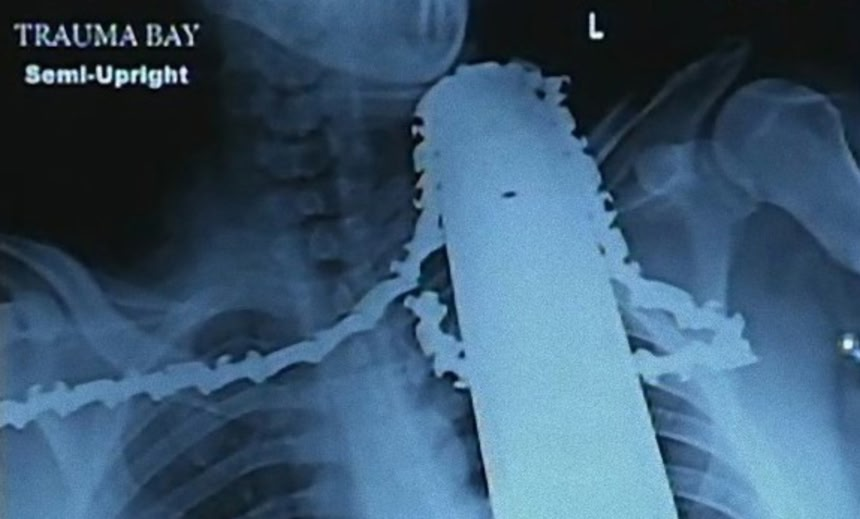

この画像を大きなサイズで見るこのレントゲン写真を見てほしい。首筋にチェーンソーが刺さったままの状態となっている。米ペンシルベニア州ロス・タウンシップでにて、民家の木の伐採をしていたジェームズ・ヴァレンタイン(21)は、ひょんなはずみで使用していたチェーンソーが突如手前に跳ね上がり首を直撃、左肩から首筋にかけてチェーンソーがガリガリと食い込んでしまったという。

救急隊員のグレッグ・ポーターが駆けつけたとき、ジェームズは完全に串刺し状態だったが意識はあったらしい。とても信じられないことだ。すぐにエンジンは取り外されたが、のこぎりの刃とチェーンはジェームズの体内に残したまま病院に搬送した。うっかり抜くと大出血を引き起こす恐れがあるからだ。

この画像を大きなサイズで見る担当医と救急医は、もしチェーンソーがあと1インチか2インチ、ずれて刺さっていたら、まったく違う結果になっていただろうと言った。チェーンソーを首から取り除く手術は、頸動脈や神経に近いことからかなりの技術が必要とされた。縫合は30針に至ったそうだ。

この画像を大きなサイズで見るジェームズの場合、幸いなことに致命的な箇所はすべてのこぎりの刃から奇跡的にはずれていたのだ。「突然バチンと何かがはじかれたような音がし、次の瞬間にはちぎれたチェーンと滴り落ちる血が目に飛び込んできた。」、「確かに最悪の事態になっていた可能性はあった。誰かがぼくのことを勘弁してやろうと思ってくれたのだろう。」、と回復しつつあるジェームズは語った。